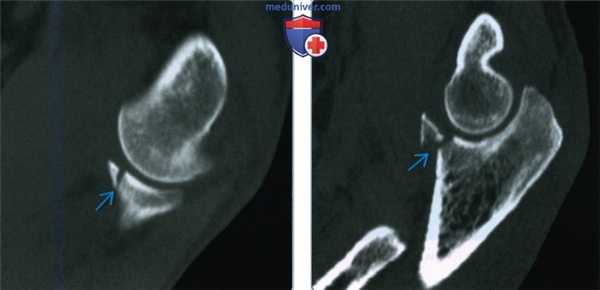

(Слева) На сагиттальной 2D КТ с реформатированием виден перелом верхушки венечного отростка с минимальным смещением. Это повреждение I типа по Регану/Моррею, которое обычно лечится консервативно.

(Справа) На сагиттальной 2D КТ с реформатированием виден перелом с захватом 50% венечного отростка. Это повреждения II типа в системе классификации Регана/Моррея. Операция при повреждениях II типа зависит от клинической оценки стабильности локтевого сустава.